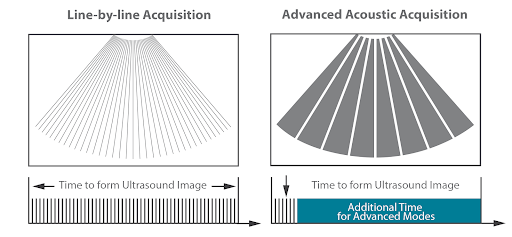

С помощью передачи и получения сигналов от относительно небольшого количества крупных зон при создании усовершенствованных акустических изображений извлекается больше информации для каждого кадра и построение изображения происходит в 10 раз быстрее, чем при традиционном построчном способе формирования ультразвукового пучка.